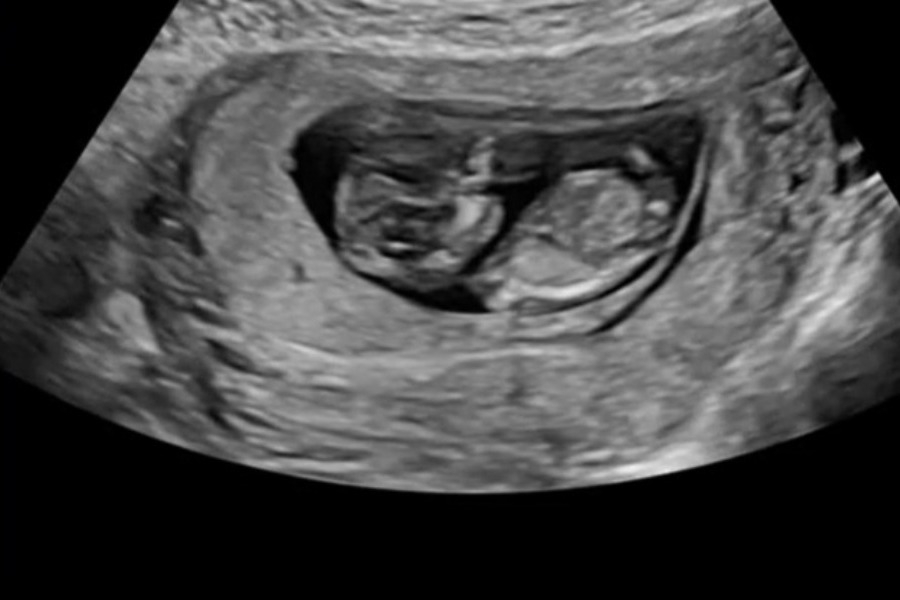

Μια έγκυος γυναίκα από το Άινταχο έγινε viral όταν μοιράστηκε στο TikTok ένα βίντεο που δείχνει τι συμβαίνει στο μωρό μέσα στη μήτρα όταν η μητέρα γελάει.

Η Destinie Ross (@destiniesanchez51) ανέβασε ένα απόσπασμα από τον υπέρηχό της, όπου φαίνεται το έμβρυο να πηδάει πάνω-κάτω κάθε φορά που εκείνη ξεσπά σε γέλια. «Απλώς για να ξέρετε, αυτό συμβαίνει στο μωρό σας όταν γελάτε… το έμαθα με τον δύσκολο τρόπο», έγραψε στη λεζάντα του βίντεο.

Η Ross αποκάλυψε πως βρισκόταν στη 11η εβδομάδα της εγκυμοσύνης και ένιωθε αγχωμένη πριν τον υπέρηχο, όμως η στιγμή γέμισε γέλιο όταν η υπερηχογράφος της ανέφερε ότι το μωρό φαίνεται να έχει λόξιγκα. «Ενώ στο βίντεο μοιάζει βίαιο, στην πραγματικότητα τα μωρά το απολαμβάνουν», είπε. «Όταν γελάμε, απελευθερώνεται σεροτονίνη, κάτι που τα κάνει να νιώθουν ηρεμία και ασφάλεια. Παρότι φαίνεται να ταρακουνιούνται λίγο, έχουν τόσο πολύ υγρό και “μαξιλάρι” γύρω τους που δεν κινδυνεύουν καθόλου». Η ίδια μάλιστα είπε πως δεν μπορούσε να σταματήσει να γελάει όταν είδε την οθόνη, με τη γιατρό της να σχολιάζει αστειευόμενη «σεισμός!» κάνοντάς την να χαλαρώσει εντελώς.

Το βίντεο έχει ξεπεράσει τις 18 εκατομμύρια προβολές και έχει προκαλέσει πληθώρα σχολίων από άλλες μαμάδες που μοιράστηκαν παρόμοιες εμπειρίες. Ορισμένες ανησύχησαν μήπως το μωρό πονάει, ενώ άλλες αστειεύτηκαν για τα δίδυμα που «χοροπηδούν μεταξύ τους». Η ειδικός υπερήχων Jenna Hopkins εξήγησε στο Newsweek πως το γέλιο προκαλεί δονήσεις που το μωρό νιώθει σαν απαλό λίκνισμα, παρόμοιο με αυτό που δημιουργεί η τεχνική κίνησης του αισθητήρα κατά τη διάρκεια της εξέτασης. Η Ross, συγκινημένη από την απήχηση, δήλωσε πως δεν περίμενε να γίνει τόσο γνωστό το βίντεο και πως η θετική ανταπόκριση –ακόμα και από διασημότητες– ήταν «απλώς απίστευτη».